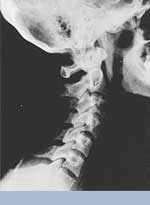

Phase Three Subluxation Degeneration is caused by subluxations that have been continuing on for between 40 and 65 years. This phase has all of the attributes of the previous phases, only worse. The curvatures are abnormal, the disc spaces are vastly decreased and changed. Calcium changes on the spine are abundant in this phase. Normally, people in phase three have a restricted range of motion and probably exhibit symptoms of some kind. In phase three the vertebrae show obvious changes and mutations in shape. Projections made of calcium, sometimes referred to as "spurs or lipping", can be readily seen on x-ray. Chiropractic reconstructive care for patients in phase three ranges from 2.5 years to 3.5 years. This does not mean that at the end of this time that any or all of the calcium changes will be gone. In many instances the body adapts to the presence of the calcium and positive changes can only be measured from a functional standpoint. As before, if Phase Three Subluxation Degeneration is left unchecked it slowly advances onward into the next phase.